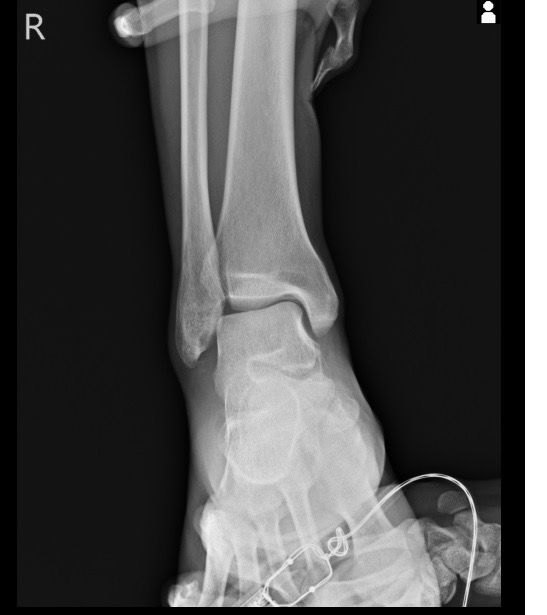

복숭아뼈 골절이 맞는 걸까요 엑스레이 사진 올립니다

3월1일 다리 접질린 후 약간의 통증과 심한 붓기 멍으로 3월7일 병원 방문. 정형와과에서 엑스레이 초음파 검사 후 골절진단 받았네요 그뒤 반깁스란 목발 받고 3일 후 다시 반깁스 하고 왔습니다 사진상에는 뼈가 떨어진 부분이 없는데 미세골절이라 그럴까요

• 2번 째 사진

사진상으로는 정확한 상태를 확인하기 어려우나 병원에서 골절 진단을 받으셨다면 골절일 가능성이 높고 엑스레이에서 뼈가 떨어진 부분이 보이지 않는다면 미세골절일 가능성이 높습니다.

미세골절 같은 경우 엑스레이상으로는 뚜렷하게 보이지 않기 때문에 검사 결과로 진단 할 수 있습니다.

엑스레이에서 뼈가 떨어진 부분이 보이지 않는다면 미세골절일 수 있습니다. 미세골절은 엑스레이에서 뚜렷하게 보이지 않지만 증상과 검사 결과로 진단할 수 있습니다.

네, 골절에는 반드시 뼈가 떨어지는 변화가 일어나는 것은 아닌데요, 미세골절의 경우에는 큰 변화가 발생하지는 않습니다.